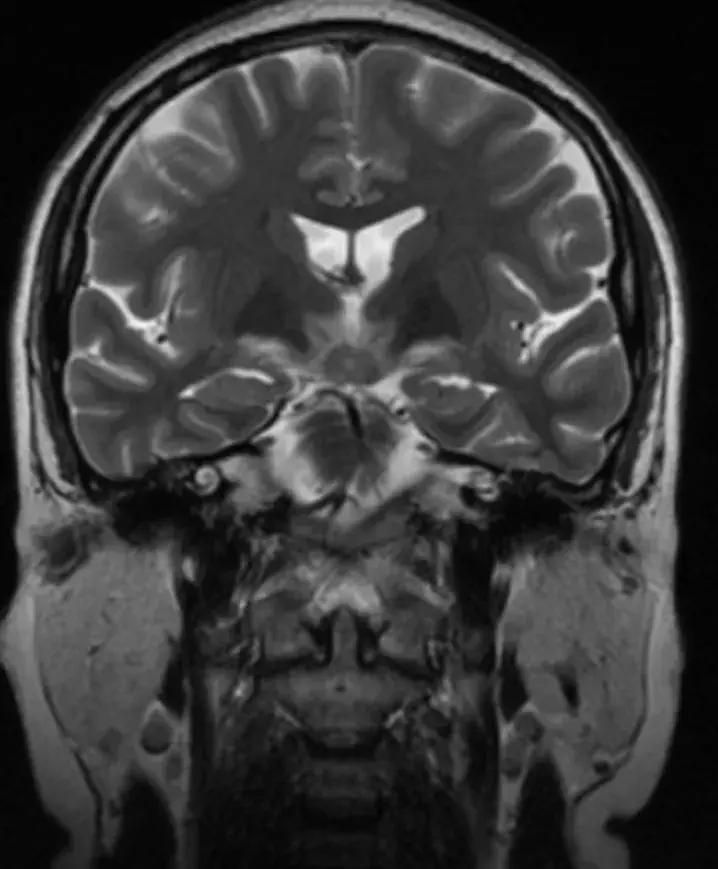

下丘脑见一类圆形异常信号灶,大小约1.6×1.4cm,T2WI呈等略高信号,T1WI呈等信号,DWI呈等信号,增强后明显异常强化,轻度压迫视交叉,FLAR见视交叉及双侧后方视束信号增高。